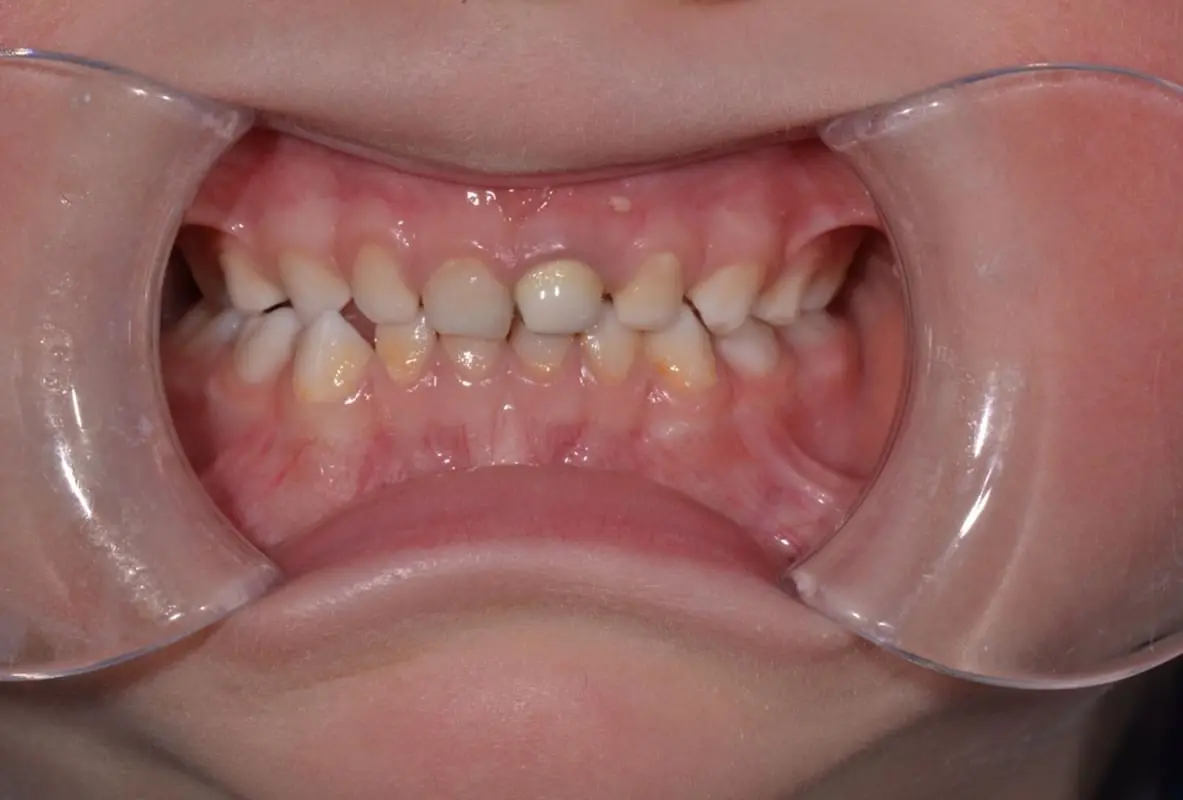

Травма - те, що може статися з будь ким і в будь який момент. А особливо це стосується дітей, які починають активно освоювати навколишнє середовище. Тому знати і вміти зреагувати на травму тимчасового зуба є стратегічно важливим для дитячого стоматолога.

Нерідко, на жаль, трапляються ситуації, коли діти травмують тимчасові зуби. В такому випадку часу на роздуми, як правило, не так багато. Рішення потрібно приймати швидко, часу на підготовку, як правило немає. Саме тому дитячому стоматологу потрібно розуміти, що потрібно робити, а що робити не потрібно. Травми коронкової частини і кореня, навколишніх тканин - що, як і коли робити? В якому випадку терміново втручатись, як коли спостерігати.